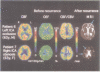

OBJECTIVES--In major cerebral arterial occlusive diseases, patients with inadequate blood supply relative to metabolic demand (misery perfusion) may be at increased risk for cerebral ischaemia. This study investigated whether patients showing misery perfusion on PET have a high risk of recurrent ischaemic stroke. METHODS--The relation between the regional haemodynamic status of cerebral circulation and the subsequent risk of recurrent stroke was prospectively evaluated in 40 patients with symptomatic internal carotid or middle cerebral arterial occlusive diseases who underwent PET. Patients were divided into two haemodynamic categories according to the mean hemispheric value of oxygen extraction fraction in the hemisphere supplied by the artery with symptomatic disease: patients with normal oxygen extraction fraction and those with increased oxygen extraction fraction (misery perfusion). All patients were followed up for at least 12 months. RESULTS--The one year incidence of ipsilateral ischaemic strokes for patients with normal oxygen extraction fraction and those with increased oxygen extraction fraction were two of 33 and four of seven patients respectively. A significantly higher incidence of ipsilateral strokes was found in patients with increased oxygen extraction fraction (Fisher's exact test; P = 0.005). In patients with increased oxygen extraction fraction, three of four strokes were watershed infarctions and the location of the infarction corresponded with the area of increased oxygen extraction fraction. CONCLUSION--These findings contradict conclusions of a previous study and suggest that patients with major cerebral arterial occlusive diseases and misery perfusion have a high risk for recurrent ischaemic stroke.